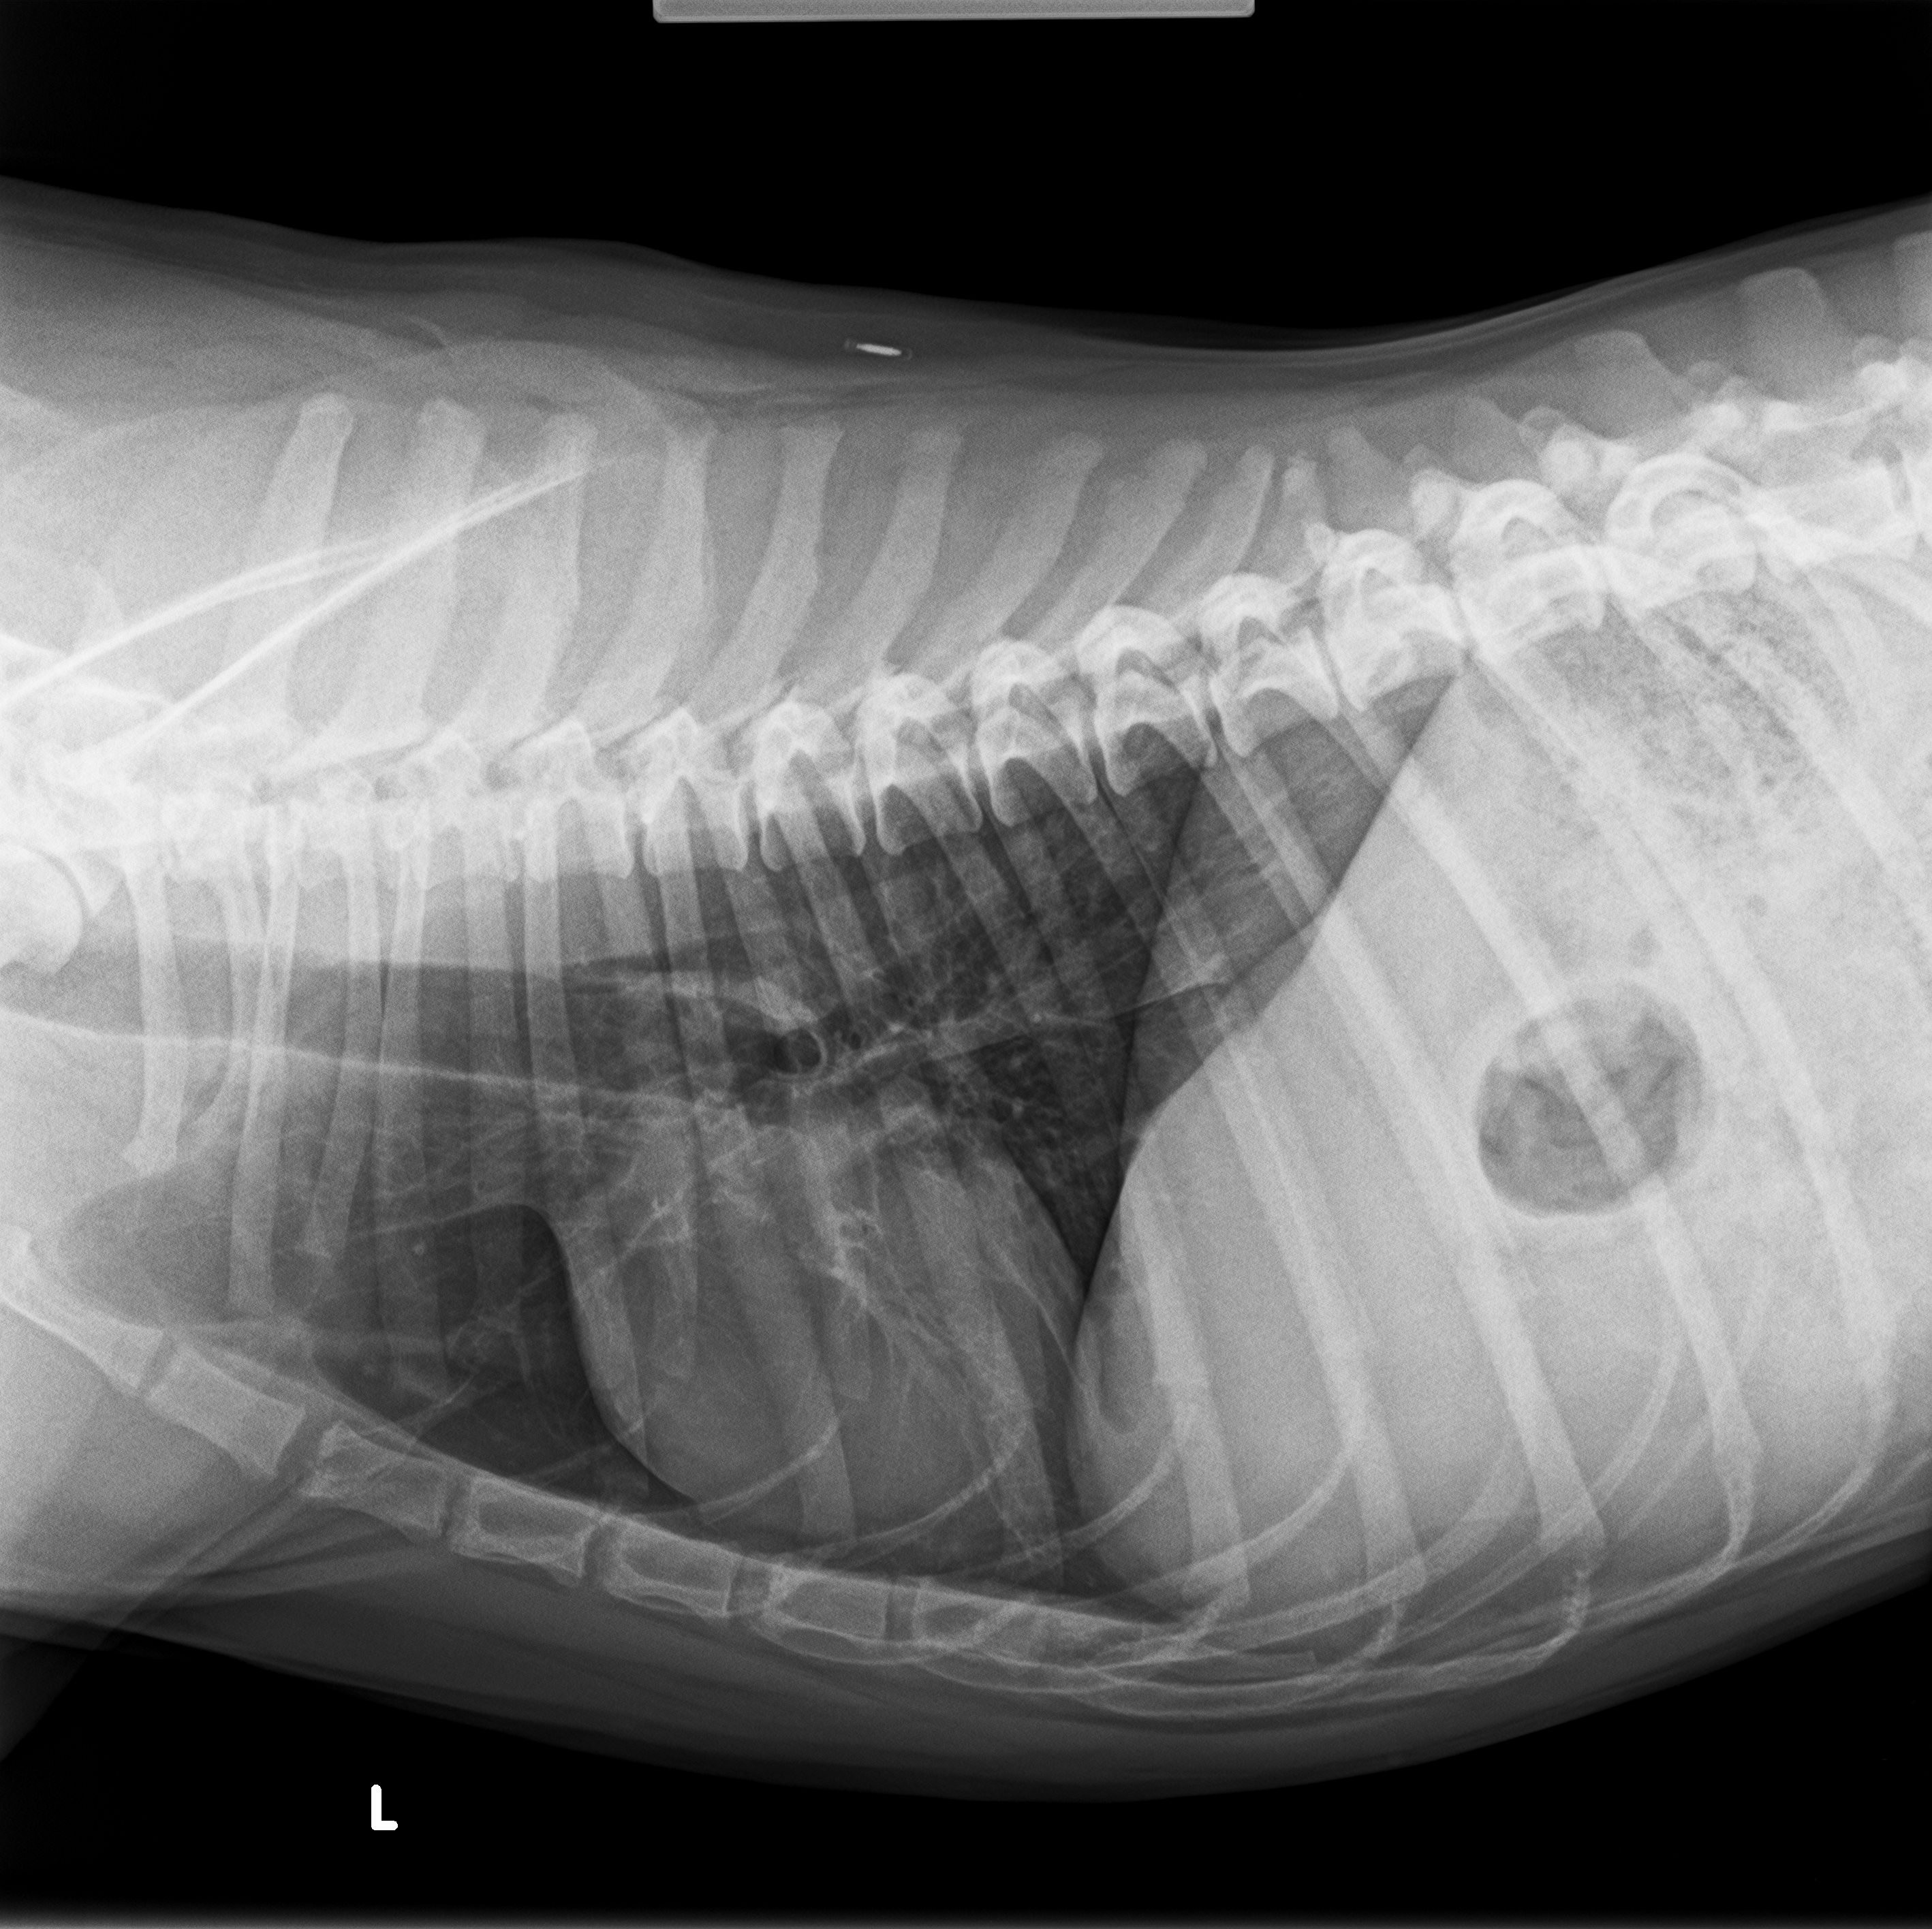

On New Year’s Eve, 12/31/25 we took Apollo into the ER because he was being far from his normal happy, energetic, playful self out of no where. We found out he had unaware tumors growing on his spleen & they had ruptured, hence why he wasn’t being himself. He had free fluid & blood everywhere it wasn’t supposed to be. The vet told us it is more than likely cancer, he told us there’s a 60% chance it was but we wouldn’t know without surgery & testing. Our options were surgery or euthanasia… even if our chances were it being 99% cancer, we absolutely had no doubt we wanted to go with surgery. Hes my husbands soul dog & the best boy a family could ask for.

Apollo went into surgery right away & he had his spleen & tumors removed! His tumors were sent away to be tested & a week later we got the worst news. It in fact was cancer. He was diagnosed with Hemangiosarcoma. Hemangiosarcoma is the most aggressive form of cancer a dog can get unfortunately. But luckily it was on a removable organ. The vet gave him 1-2 months to live.